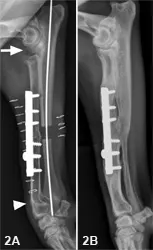

Outcome: A right radial lengthening was performed, incorporating a cortical graft obtained via ulnar ostectomy. Patient lameness and elbow pain completely resolved within 3 months postoperatively.

Figure 2. Immediate postoperative lateral view (2A) with prematurely closed right radial physis of the right radius and ulna (arrowhead) and humero-ulnar incongruity (arrow). Lateral view (2B) shows the right radius and ulna 2 years after surgery, demonstrating greatly reduced incongruity and complete healing of the radius and ulna.